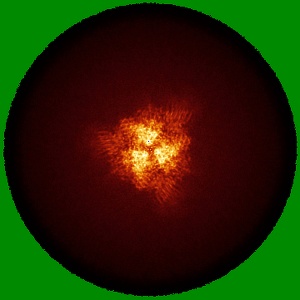

Cryo-EM structure of the SARS-CoV-2 spike protein (3-up RBD) bound to neutralizing nanobodies P86

Single-particle2.7 Å

Sample: SARS-CoV-2 spike protein (3-up RBD) bound to neutralizing nanobodies P86